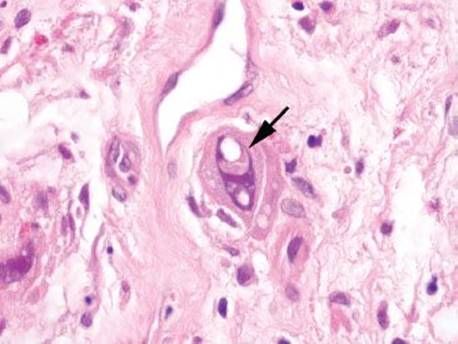

Figure 4.51 Ischemic colitis pattern. The striking finding at low magnification is the presence of “microcrypts” (arrow). Note the collapse of the hyalinized lamina propria in this area, causing a condensation of these crypts. Look at the left portion of this image for contrast to relatively normal crypts and lamina propria.

Mucosal ischemia causes a highly characteristic pattern of injury, including features of surface injury, loss of mucin, lamina propria hemorrhage and hyalinization, withered crypts, atrophic microcrypts, and lamina propria collapse (Fig. 4.50). The architectural pattern of withered crypts and microcrypts is distinctive at low magnification, and one might even refer to this pattern of injury as the “microcrypt pattern” (Fig. 4.51). Although ischemic injury is top among the differential diagnoses, other considerations include vascular injury (such as that seen in radiation colitis, amyloidosis, or vasculitis), infection (particularly Escherichia coli 0157:H7 and Clostridium difficile), and medications (NSAIDs, Kayexalate, and sevelamer).